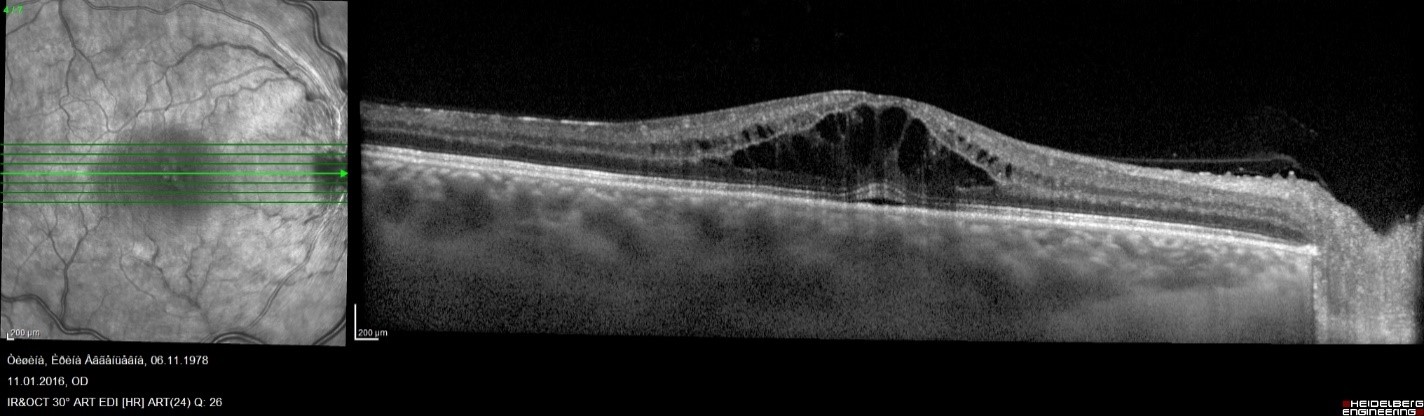

Обязательным методом обследования при обнаружении нарушения проходимости вен сетчатки является выполнение оптической когерентой томографии сетчатки (ОКТ) для оценки витреоретинального интерфейса, толщины и микроструктуры сетчатки в макулярной области, так как в 60-100% окклюзии центральной вены сетчатки и в 10% - ее ветвей, осложняются развитием макулярного отека.